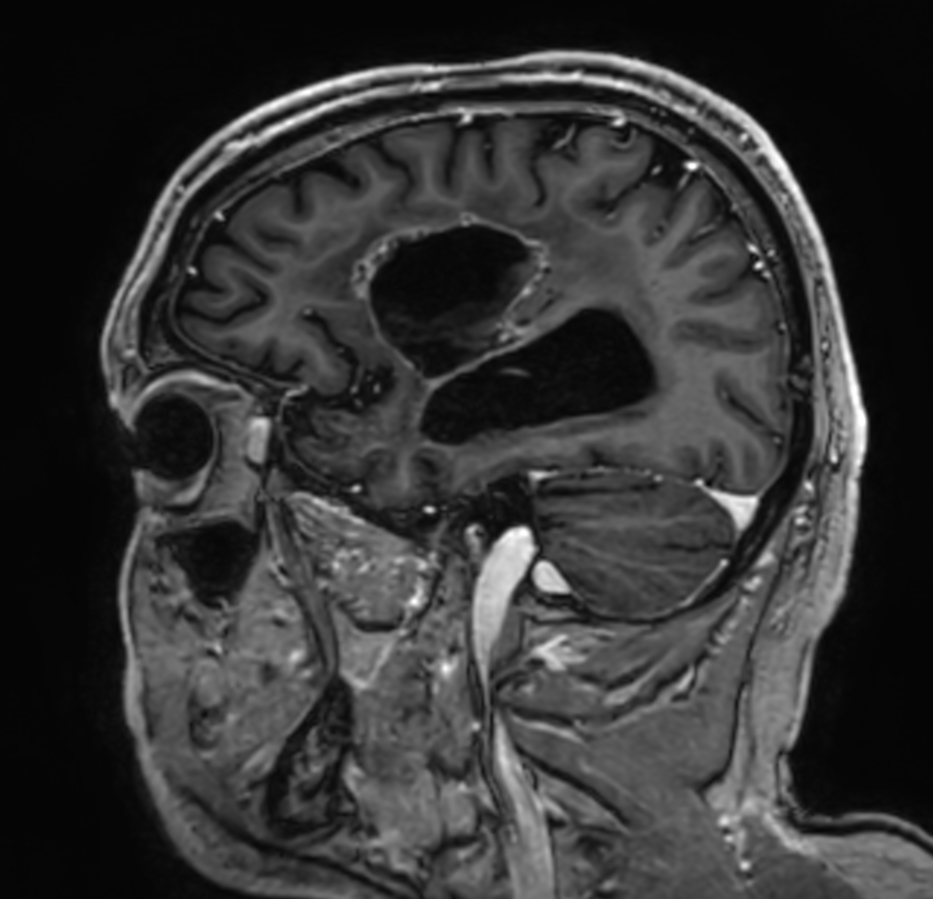

Brain glioblastoma, post-operative

Patient who was operated on glioblastoma

Sagittal 3D T1w TFE (with gado)